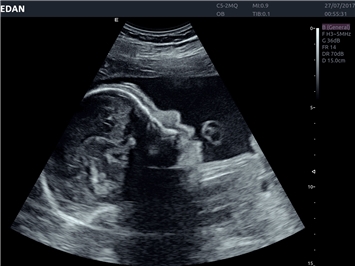

• 3D/4D-визуализация с автоматическим редактированием объема (eFace)

• Автоматизированные измерения в акушерстве

• Акушерства и гинекологии